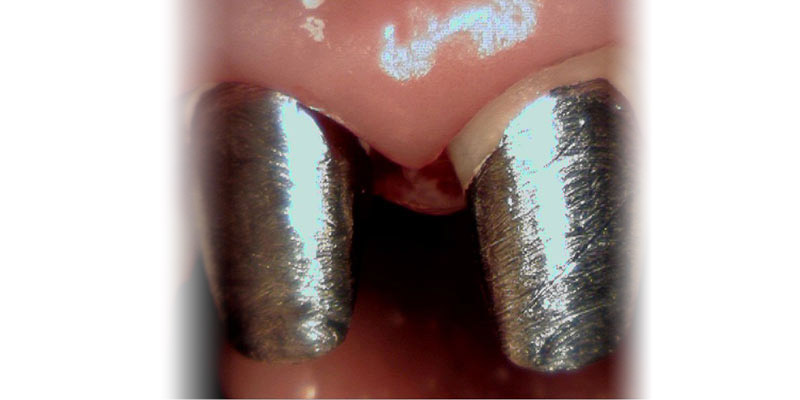

Wkłady koronowo-korzeniowe wykonuje się ze stopów różnych metali powszechnie stosowanych w protetyce. Najczęściej są to stopy metali nieszlachetnych jak również stopy złota, platyny lub tytanu. W celu wzmocnienia zęba leczonego kanałowo stosujemy również, szczególnie w strefie estetycznej, wkłady pełnoceramiczne wykonane z tlenku cyrkonu lub aluminium. Tego rodzaju wkłady wykonywane są w pracowni protetycznej po uprzednim przygotowaniu zęba i pobraniu wycisków lub zeskanowaniu wnętrza korzenia i jego obrzeży za pomocą specjalnego skanera (czytnika) wewnątrzustnego.

Wyróżniamy wkłady koronowo-korzeniowe indywidualne i standardowe. Zastosowanie odpowiednich wkładów zależne jest od sytuacji klinicznej, wkłady indywidualne wykonuje się w pracowni protetycznej po wcześniejszym opracowaniu zęba i pobraniu wycisku u Pacjenta. Wkłady standardowe, są fabrycznie przygotowywane i dostosowane do rozmiarów kanału korzeniowego, a ich osadzenie pomija pracę laboratorium protetycznego.